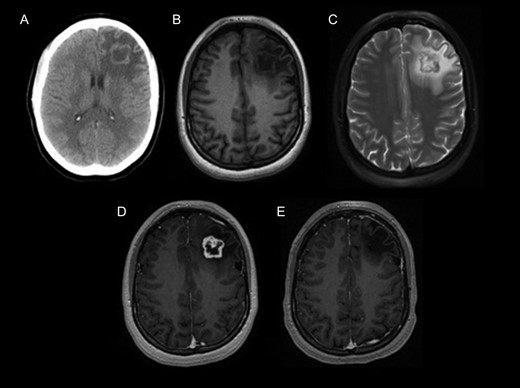

A 21-year-old woman, two years status post resection of a papillary thyroid carcinoma, presented to the emergency department with recent onset seizures. She had suffered from secondarily generalized tonic-clonic seizures that lasted for 1–2 min with a short postictal period. There was no diagnosis of neurofibromatosis and no other known genetic disorder in this patient or her family. On admission, the examination was unremarkable. She did not have any stigmata of neurofibromatosis. Neurological examination did not reveal any focal signs or deficits. Computerized tomography (CT) scans revealed a 2.6 × 2.4 cm2 heterogeneous left frontal lobe mass, with a hyperdense peripheral rim and surrounding vasogenic edema.

Magnetic resonance imaging (MRI) of the brain demonstrated an intra-axial left frontal lobe mass that was hypointense with an isointense rim on T1 (Fig. 1), mixed isointense and hyperintense on T2 (Fig. 1), with extensive surrounding vasogenic edema. The mass revealed a heterogeneous ring enhancement with a central area of non-enhancement (Fig. 1) and restricted diffusion within the wall of the mass. There was no evidence of hemorrhage or calcification observed using susceptibility-weighted MRI images or with CT imaging (Fig. 1). Although our presumptive diagnosis was a metastatic thyroid cancer, initial diagnosis also included primary high-grade glioma and lymphoma.

MRI tomography. (A) Non-contrast computed tomography shows heterogeneous left frontal lobe mass with a hyperdense peripheral rim and surrounding vasogenic edema without calcification. Pre-contrast (B) and post-contrast (C) T1-weighted MRI images, and T2-weighted MRI (D), show an intra-axial heterogeneously enhancing left frontal lobe mass with surrounding vasogenic edema. (E) 5-Year postoperative T1-weighted post-contrast MRI shows gross total resection of the tumor without recurrence.

A decision for microsurgical resection was made. The patient underwent a left frontal craniotomy. Gross total resection was achieved (Fig. 1). The intraoperative interpretation was a low-grade spindle cell neoplasm consistent with low-grade astrocytoma. The patient tolerated the surgery well, with an uneventful postoperative course. She was discharged home without any complications. A 6-year post-surgery follow-up did not reveal recurrence or neurologic deficit. The pathology from paraffin embedded tissue sections revealed a well-circumscribed spindle cell neoplasm, with a biphasic pattern of hypo and hyper-cellularity, surrounded by a thin rim of gliotic cerebral parenchyma. The spindle cells contained scant cytoplasm and elongated nuclei (Fig. 2). Focally a palisaded pattern was suggested. Abundant hyalinized blood vessels were also present. These were diagnostic features of a schwannoma with no anaplastic properties.